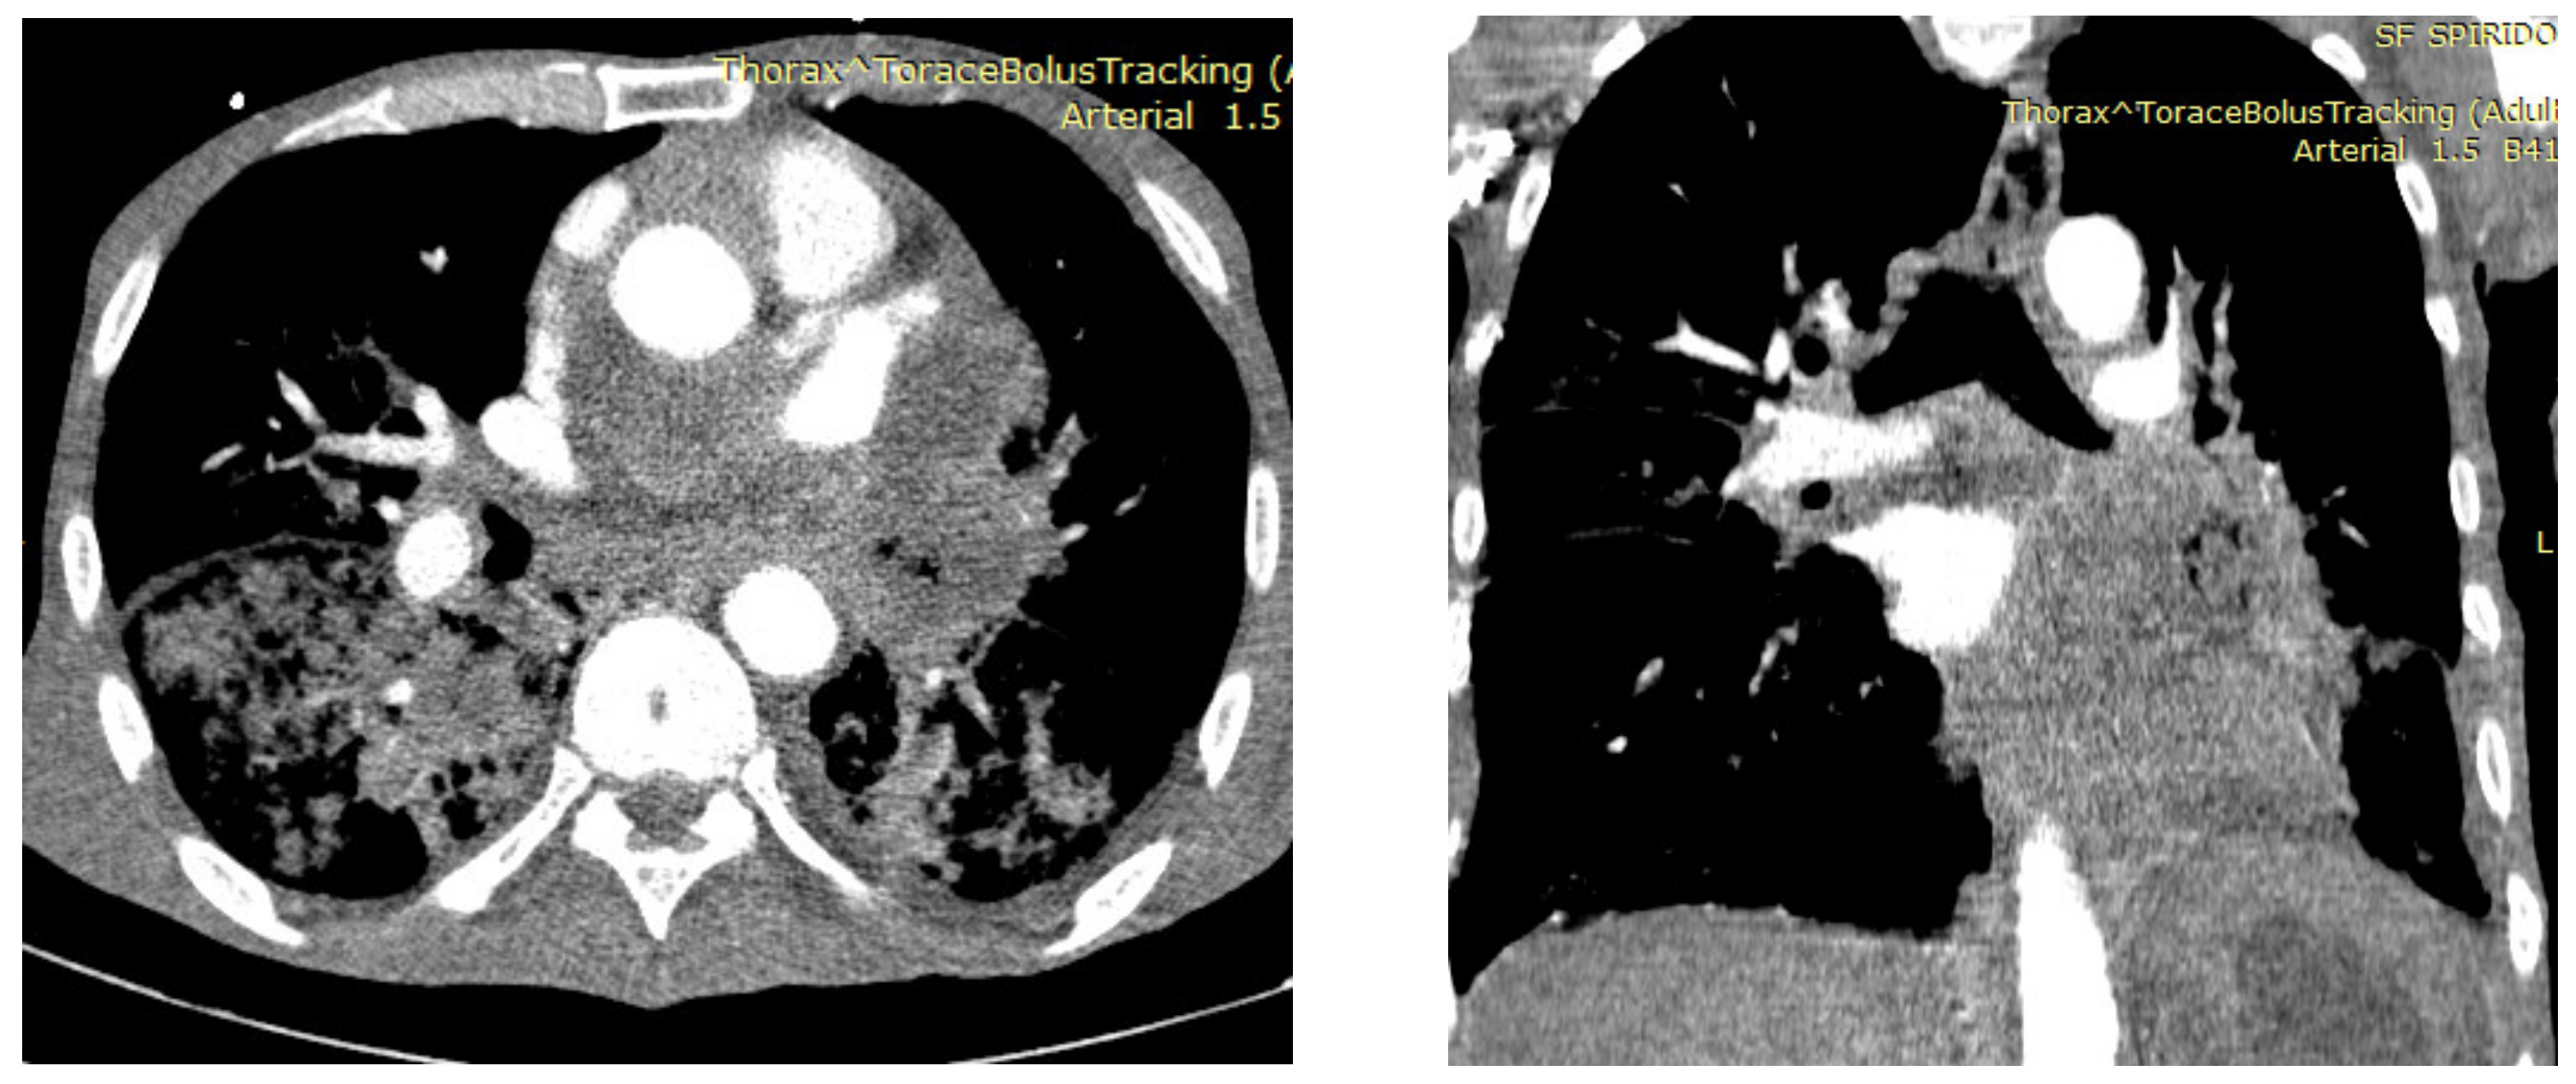

2. Gas Pulmonary Embolism

2.3. Diagnosis

| Computer tomography | Small amount of air in the main pulmonary artery, on the right heart or systemic veins; in severe cases, pulmonary hypertension and right heart strain are found | Ground-glass opacities, interlobar septal thickening with the pattern of “crazy paving” | Diffuse bilateral ground-glass opacities | Bilateral lung nodules, located mainly in the peripheral lung areas and in the lower lobes, mediastinal or hilar lymphadenopathy, a dilated pulmonary branch (mycotic aneurysm) and feeding vessel sign | The classic finding (affected centrilobular arteries) is an image of “tree-in-bud”; in cases where the main arteries are affected, the findings are filling defects that resemble acute or chronic pulmonary emboli |